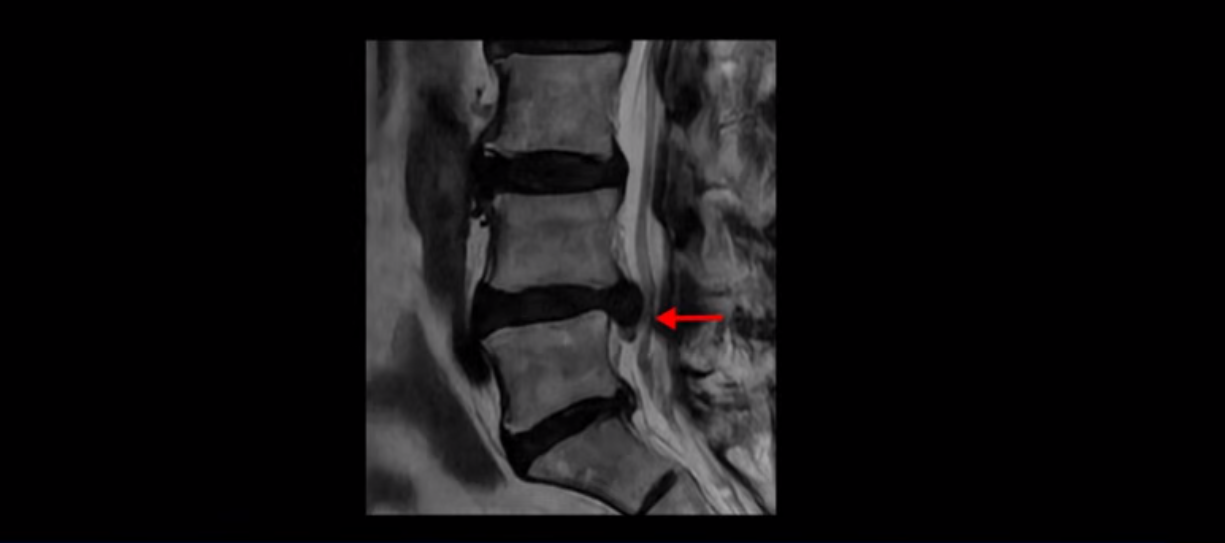

이분 MRI를 먼저 보실까요. 보시다시피 척추 여러 마디가 퇴행되어 있고

4번 5번 마디에는 심한 디스크 파열이 있습니다.

밀려 나온 수핵이 밑으로 흘러내려가 있는데, 이분의 증상은 급성 디스크 증상은 없고 협착증 증상이라서 이 디스크 파열은 오래전에 발생해서 이미 밀려 나온 수핵이 흡수되지 않고 굳어있는 상태로 보입니다.

단면을 보면 디스크 수핵은 왼쪽으로 심하게 밀려 나와 있고

이렇게 신경 공간이 좁아진 것을 협착이라고 합니다. 왼쪽으로 신경 구멍이 더 좁아져 있으니까 처음에는 왼쪽 엉덩이와 다리가 아팠는데 몇 년 동안 주사 맞으면서 버티다 보니까 오른쪽 다리까지 아프게 됩니다. 결국 양쪽 다리가 너무 아파서 5분 걷기도 힘들어지게 됩니다.

이분의 MRI를 환자 증상은 자세히 듣지 않고 MRI만 보고 진료하는 의사가 본다면 심한 디스크 파열이 보이기 때문에 그냥 디스크 파열 증상이라고 진단할 겁니다. 하지만 이분의 증상은 명확히 디스크 탈출 증상이 아니고 협착증 증상입니다. 급성 디스크 증상이라면 재채기도 못하고 조금만 허리를 구부려도 날카로운 통증이 발생할 텐데, 그런 증상이 아닙니다. 진단을 잘못하면 엉뚱한 치료를 하게 되고 당연히 치료 결과가 좋을 수가 없습니다. 그래서 밀려 나온 디스크와 협착이 같이 보일 때는 증상으로 질환을 감별하는 것이 매우 중요합니다. 오래되어 굳어버린 디스크 수핵도 신경을 좁히는 역할을 하니까 협착증 증상을 일으키는 것이죠.